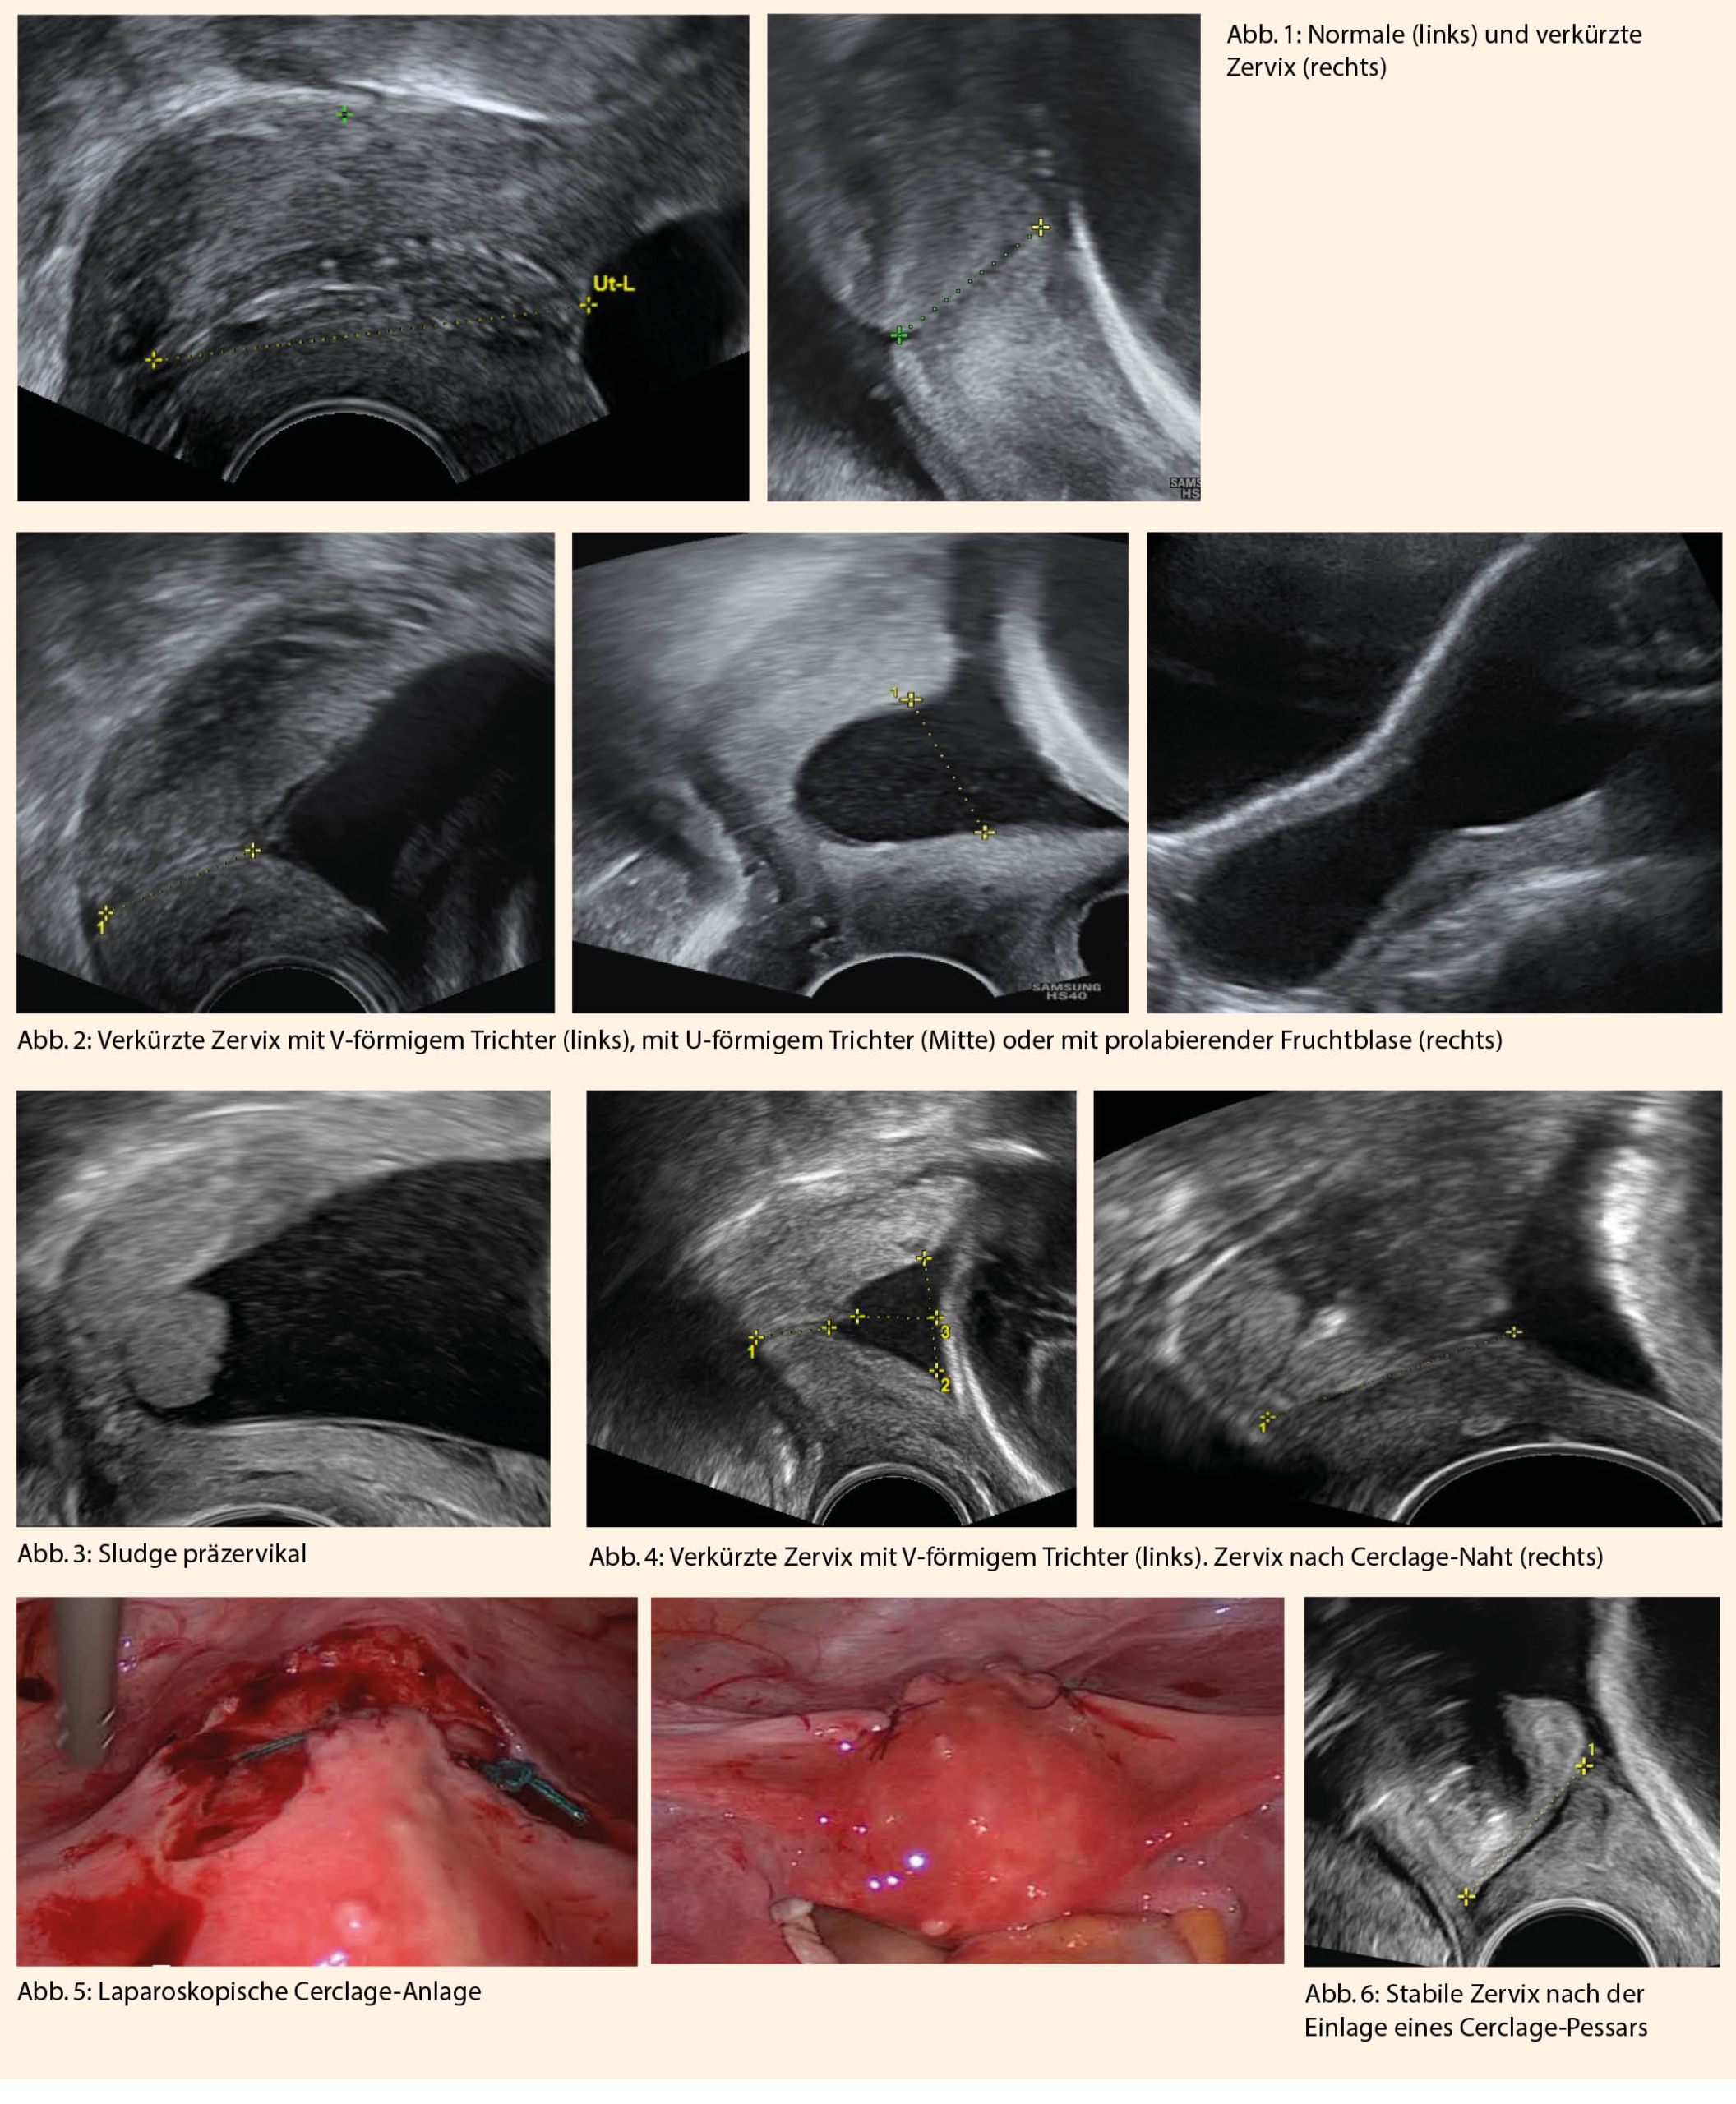

Die geeignetste Untersuchung zur Diagnosestellung einer Zervixinsuffizienz ist die sonographische Bestimmung der Zervixlänge. Es ist eine effektive, günstige und einfach reproduzierbare Untersuchung, welche der vaginalen Tastuntersuchung überlegen ist. Im Rahmen der zweiten Ultraschalluntersuchung zwischen der 20. Und 23. Schwangerschaftswoche wird unter anderen die Zervixlängemessung empfohlen (3) (Abb.1 links). Eine Zervixlänge unter 25mm wird als verkürzt definiert und ist mit einem erhöhten Risiko für eine Frühgeburt assoziiert. (Abb.1 rechts).

Neben der Zervixlänge können auch weitere Charakteristika wie die Weichheit des Zervixgewebes und die Trichterbildung sonopalpatorisch überprüft werden. Ein Trichter ist ein typisches Zusatzmerkmal einer verkürzten Zervix und das sonographische Bild kann je nach Ausprägungsgrad der Insuffizienz variieren. Ein beginnender Trichter kann ein T- oder V-förmiges Schema haben (Abb. 2 links), während eine U-förmige Zervix (Abb. 2. Mitte) bzw. eine sanduhrförmige prolabierende Fruchtblase (Abb. 2. rechts) Hinweise einer fortgeschrittenen Zervixinsuffizienz sind. Zusätzlich kann manchmal innerhalb des Trichters Sludge präzervikal nachgewiesen werden. Sludge wird als eine hyperechogene fluktuierende Ansammlung vor dem Os internum definiert und besteht aus fetalem Epithel, Vernix, Leukozyten und/oder Bakterien (Abb. 3). Sludge gilt nicht nur als zusätzlicher Risikofaktor für eine drohende Frühgeburt sondern auch für eine potenziell bereits stattgefundene mikrobielle Invasion der Amnionhöhle mit beginnender Chorioamnionitis (4).

Die primäre Anlage einer prophylaktischen Cerclage kann bei Schwangeren mit Einlingsgravidität und Status nach einer oder mehreren Frühgeburt(en) bzw. Spätabort(en) in Erwägung gezogen werden (6). Die Operation wird in der Regel am Anfang des zweiten Trimesters durchgeführt. Im Rahmen einer prophylaktischen Cerclage bietet die Durchführung eines gleichzeitigen totalen Muttermundsverschlusses eine zusätzliche Option zur Prolongation der Schwangerschaft durch einen Schutz gegen aszendierende Infektionen. Am häufigsten werden die Cerclage nach McDonald oder nach Shirodkar mit oder ohne einen totalen Muttermundsverschluss angewendet (Abb. 4). Beide transvaginalen Techniken haben ein ähnlich gutes Outcome, was die perinatale Morbidität und Mortalität betrifft (7). Die Cerclage wird ca. 3 Wochen vor dem errechneten Geburtstermin wieder entfernt.

Eine abdominale Cerclage kann sowohl durch Laparotomie als auch laparoskopisch eingelegt werden (Abb. 5).

Eine günstige und komplikationsarme therapeutische Methode, welche gemäss mehreren prospektiv randomisierten Studien zu tieferen Frühgeburtsraten bei Zervixinsuffizienz führen kann, ist die Anwendung eines Cerclage-Pessars (11). Durch eine Sakralisierung der Portio (Veränderung der Achse des Zervixkanals zur Achse der Vagina) wird eine Druckentlastung und mechanische Stabilisierung des Gewebes erreicht (Abb. 6).